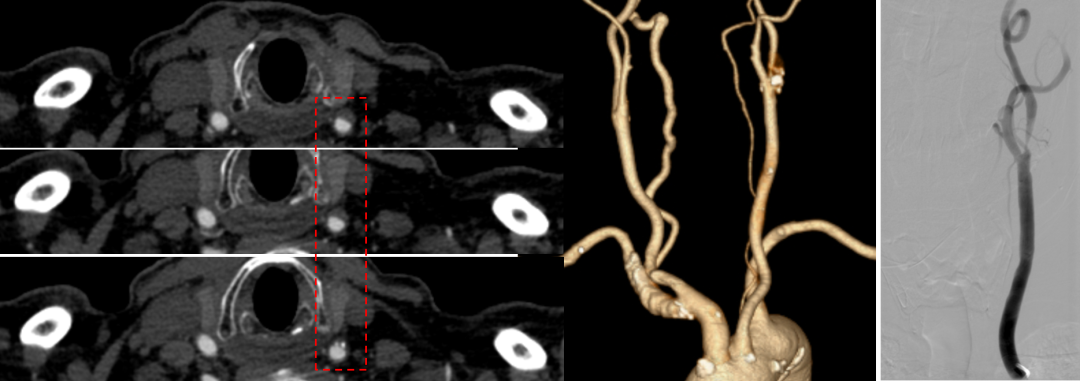

假性闭塞病例9例。这印证了TCAR相较于TFCAS在处理复杂病变(如假性闭塞)时的理论优势,因为逆向血流保护能有效避免栓子通过病变段。

碎屑捕获率:捕获率达到55.88%。这是一个非常震撼的数据。相较于TFCAS术中栓塞保护装置下仍可能发生的“隐形栓塞”,TCAR的逆向血流保护机制能有效将脱落的斑块碎屑逆流引出体外,过滤器内可见肉眼及镜下碎屑,直接证实了其卓越的脑保护效果。

穿刺点区域存在严重的附壁血栓或环形钙化,荷包缝合困难且易导致栓塞。

斑块评估是核心:TCAR围手术期安全性的关键,在于术前对斑块形态学和斑块稳定性的精准判断。一个好的影像评估(斑块负荷、钙化特征、溃疡/血栓)胜过术中万般补救。